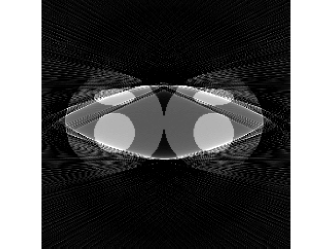

In practice, when pi=0subscript𝑝𝑖0p_{i}=0, we do not know whether this projection ray is saturated or does not hit the object. Thus, the ISD scheme proposed in Section II-C should be used together with M1bit-CSR (abbreviated as M1bit-CSR-ISD). Again consider the projections shown in Fig.1. Fig.7 displays the detected ΨΨ\Psi. The difference between the ideal and the detected ΨΨ\Psi is shown in Fig.7, where the false detections (zero measurements that are detected as saturated ones) are marked in blue and missing detection (saturated measurements that are regarded as zero ones) are in green.

Figure 7: Saturation indicator ΨΨ\Psi for saturated data shown in Fig.1: (a) the true ΨΨ\Psi; (b) indicator detected by M1bit-CSR-ISD; (c) difference between the true and the detected saturation indicator (blue: false detection; green: missing detection).